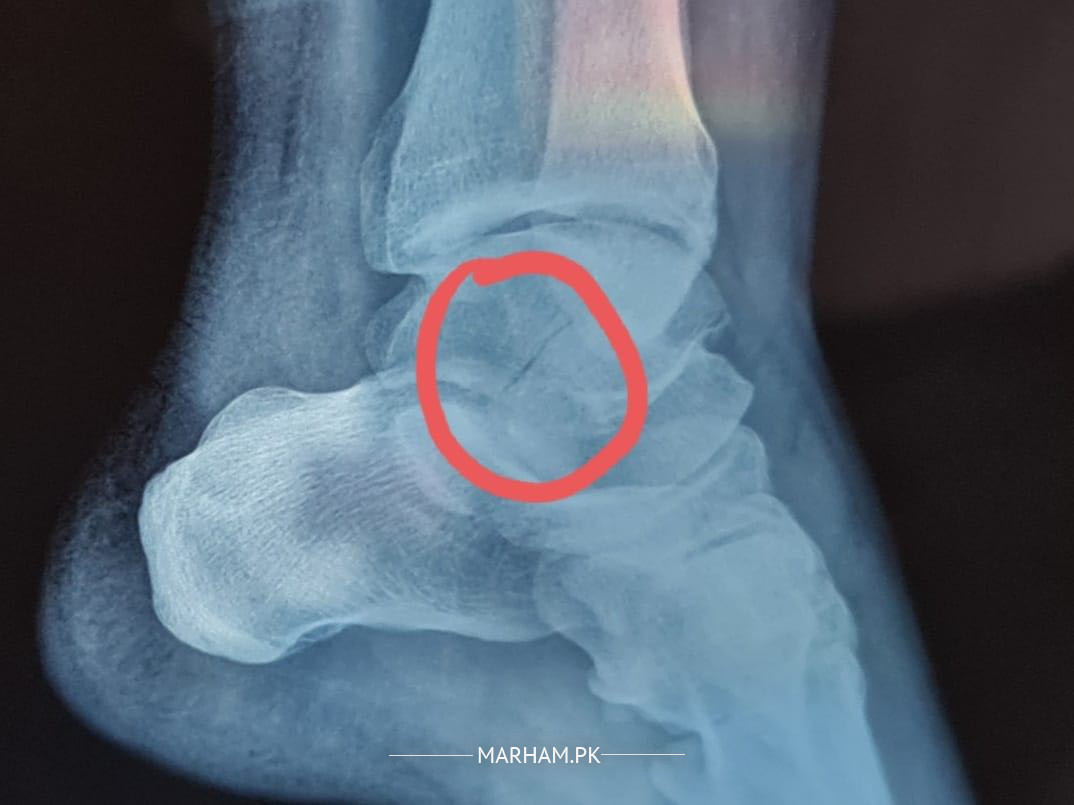

My husband fell down from stairs and had a fracture in his talus bone. The doctors are saying that we need to operate it and insert screws to fix the bone that has been cracked and dislocated. Can it be fixed without operation only with plaster. Xray has been attached kindly advise